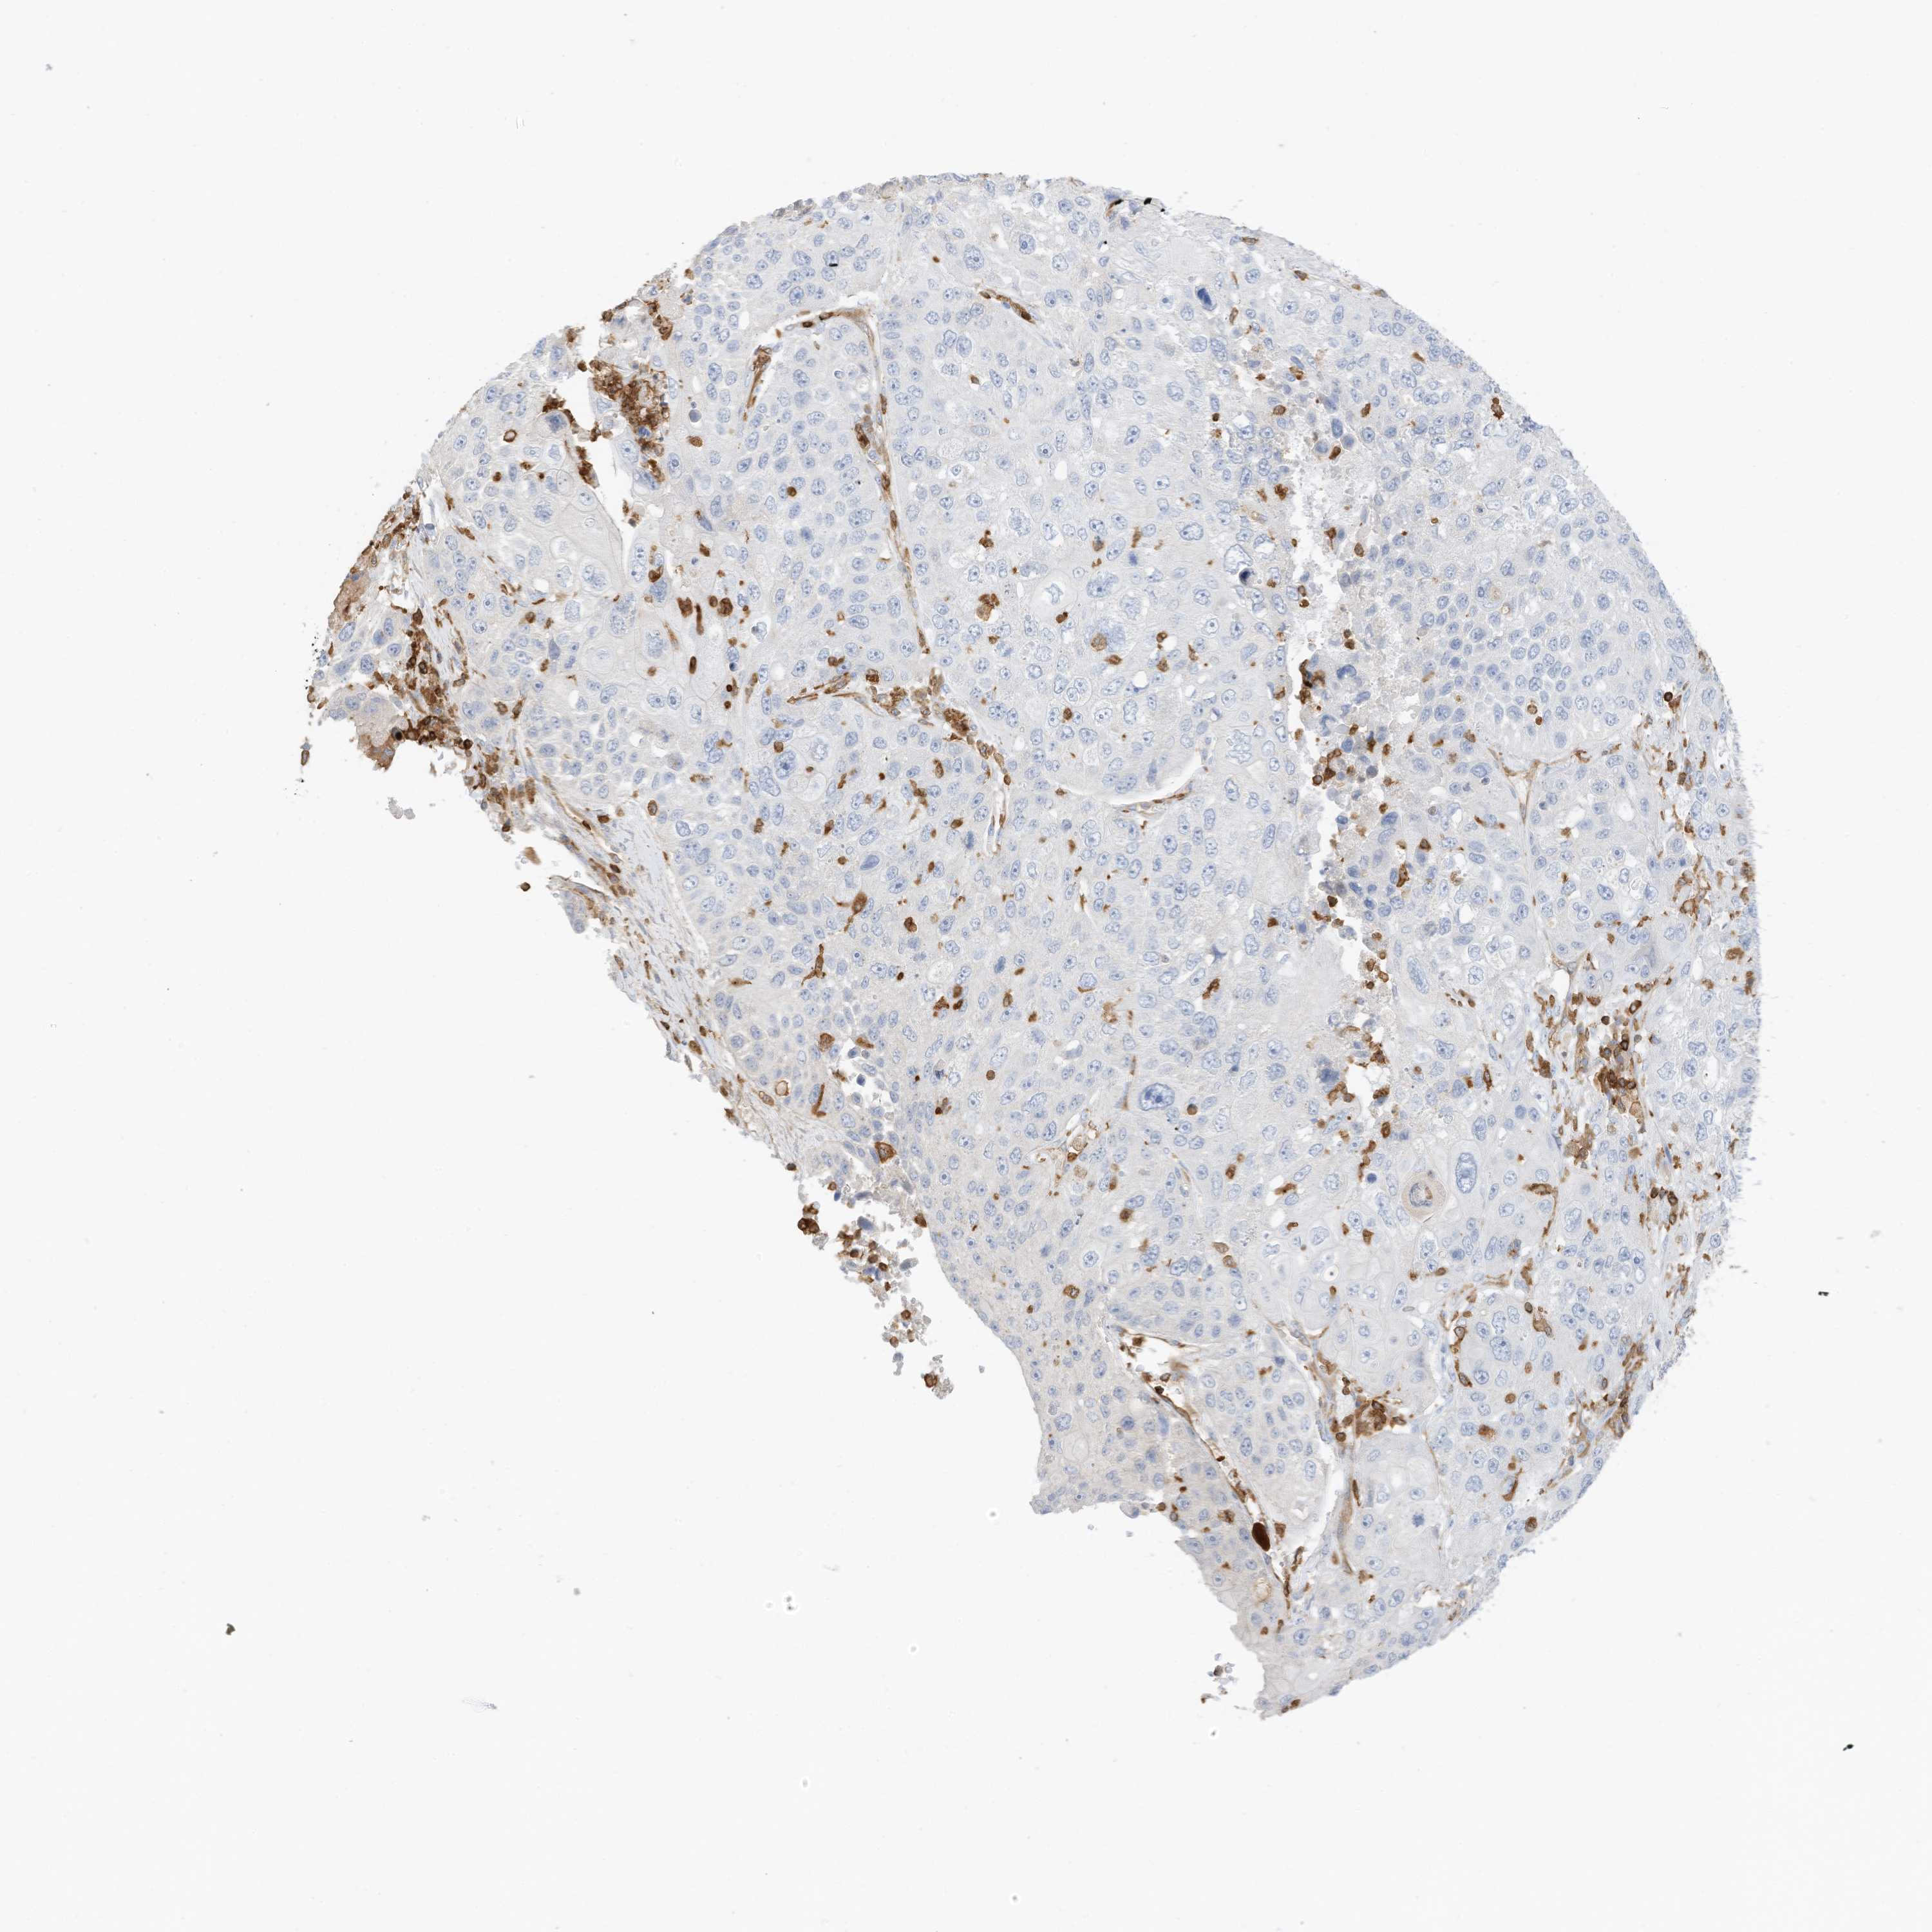

LUNG ADENOCARCINOMA (TCGA) - Interactive survival scatter ploti

The Survival Scatter plot shows the clinical status (i.e. dead or alive) for all individuals in the patient cohort, based on the same data that underlies the corresponding Kaplan-Meier plots. Patients that are alive at last time for follow-up are shown in blue and patients who have died during the study are shown in red.

The x-axis shows the expression levels (FPKM) of the investigated gene in the tumor tissue at the time of diagnosis. The y-axis shows the follow-up time after diagnosis (years). Both axes are complimented with kernel density curves demonstrating the data density over the axes. The top density plot shows the expression levels (FPKM) distribution among dead (red) and alive patients (blue). The right density plot shows the data density of the survived years of dead patients with high and low expression levels respectively, stratified using the cutoff indicated by the vertical dashed line through the Survival Scatter plot. This cutoff is automatically defined based on the FPKM cutoff that minimizes the p-score. The cutoff can be changed by dragging the vertical line or by entering a cutoff value in the square labeled "Current cut-off".

Under the Survival Scatter plot the p-score landscape (black curve; left axis) is shown together with dead median separation (red curve; right axis). Dead median separation is the difference in median mRNA expression between patients who have died with high and low expression, respectively. It is calculated as follows: median FPKM expression of dead patients with high expression - median FPKM expression of dead patients with low expression. This is intended to aid the user in visually exploring custom cutoffs and the associated p-scores and dead median separation.

Individual patient data is displayed and can be filtered by clicking on one or more of the category buttons on the top of the page. Categories describing expression level and patient information include: high, low, alive, dead, female, male and tumor stages. The scale of the x-axis can be toggled between linear and log-scale by clicking on the "x log" button. Mouse-over function shows TCGA ID, patient information and mRNA expression (FPKM) for each patient.

& Survival analysisi

Kaplan-Meier plots summarize results from analysis of correlation between mRNA expression level and patient survival. Patients were divided based on level of expression into one of the two groups "low" (under cut off) or "high" (over cut off). X-axis shows time for survival (years) and y-axis shows the probability of survival, where 1.0 corresponds to 100 percent.

ARHGAP25 is potential prognostic, high expression is favorable in Lung Adenocarcinoma (TCGA)